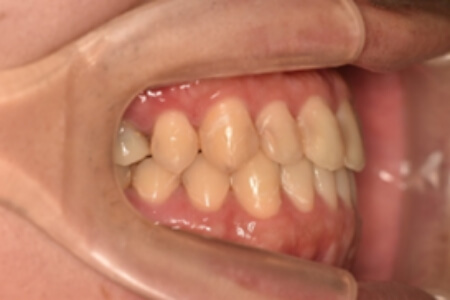

| 治療内容の詳細 | 初診時26歳の男性で、受け口を気にされ来院されました。 検査の結果、下顎前突、上顎前歯部叢生および上顎側切歯反対咬合を伴うアングルⅢ級不正咬合と診断しました。 先ず、前期治療として、リンガルアーチを使用し、上顎中切歯を前方へ移動させ、反対咬合の改善を行いました。 その後、マウスピース型矯正装置(インビザライン)で配列を行いました。 治療期間としては1年8か月でした。 |